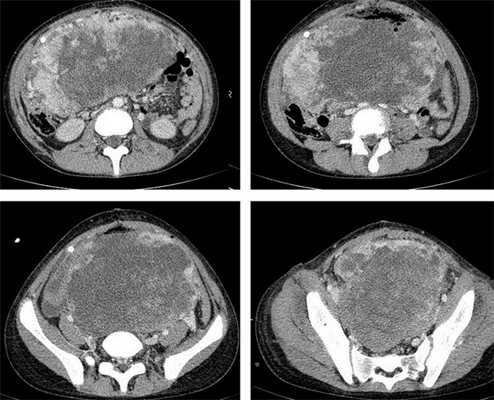

Яичники

Овариальные (расположенные в яичниках, яичниковые) опухоли наиболее часто проявляются болью в животе. При осмотре пальпируется опухоль в малом тазу, часто - в брюшной полости. Также за счет асцита (скопления в брюшной полости жидкости) увеличен живот. Нередко у девочек с таким диагнозом бывает лихорадка.

Самая часто диагностируемая герминогенная опухоль - это дисгерминома. Преимущественно ее обнаруживают во второй декаде жизни. У маленьких девочек встречается редко. Такое заболевания сравнительно быстро распространяется, поражая брюшину и второй яичник. Обычно новообразования односторонние, имеют большие размеры. В связи с этим частое явление - разрыв капсулы новообразования.

- УЗИ. «Ультразвук» нужен для того, чтобы выявить первичный очаг как гонадной (в половых органах), так и внегонадной герминогенной опухоли. Его также проводят в ходе терапии, чтобы оценить ее эффективность.

- КТ (расшифровка: компьютерная томография), МРТ (расшифровка: магнитно-резонансная томография), ПЭТ-КТ (расшифровка: позитронно-эмиссионная томография, совмещенная с КТ). Эти обследования необходимы, чтобы рассмотреть структуры организма послойно и визуализировать опухоль. Они показывают, как сильно распространен патологический опухолевый процесс на находящиеся рядом ткани и органы, есть ли поражение костей. КТ - это самый чувствительный метод для обнаружения метастазов в легких. Проведение МРТ и КТ головного мозга необходимо, чтобы обнаружить и визуализировать герминогенные новообразования эпифиза.

Рисунок 8. КТ органов брюшной полости - на снимках вы можете увидеть опухоль яичника.